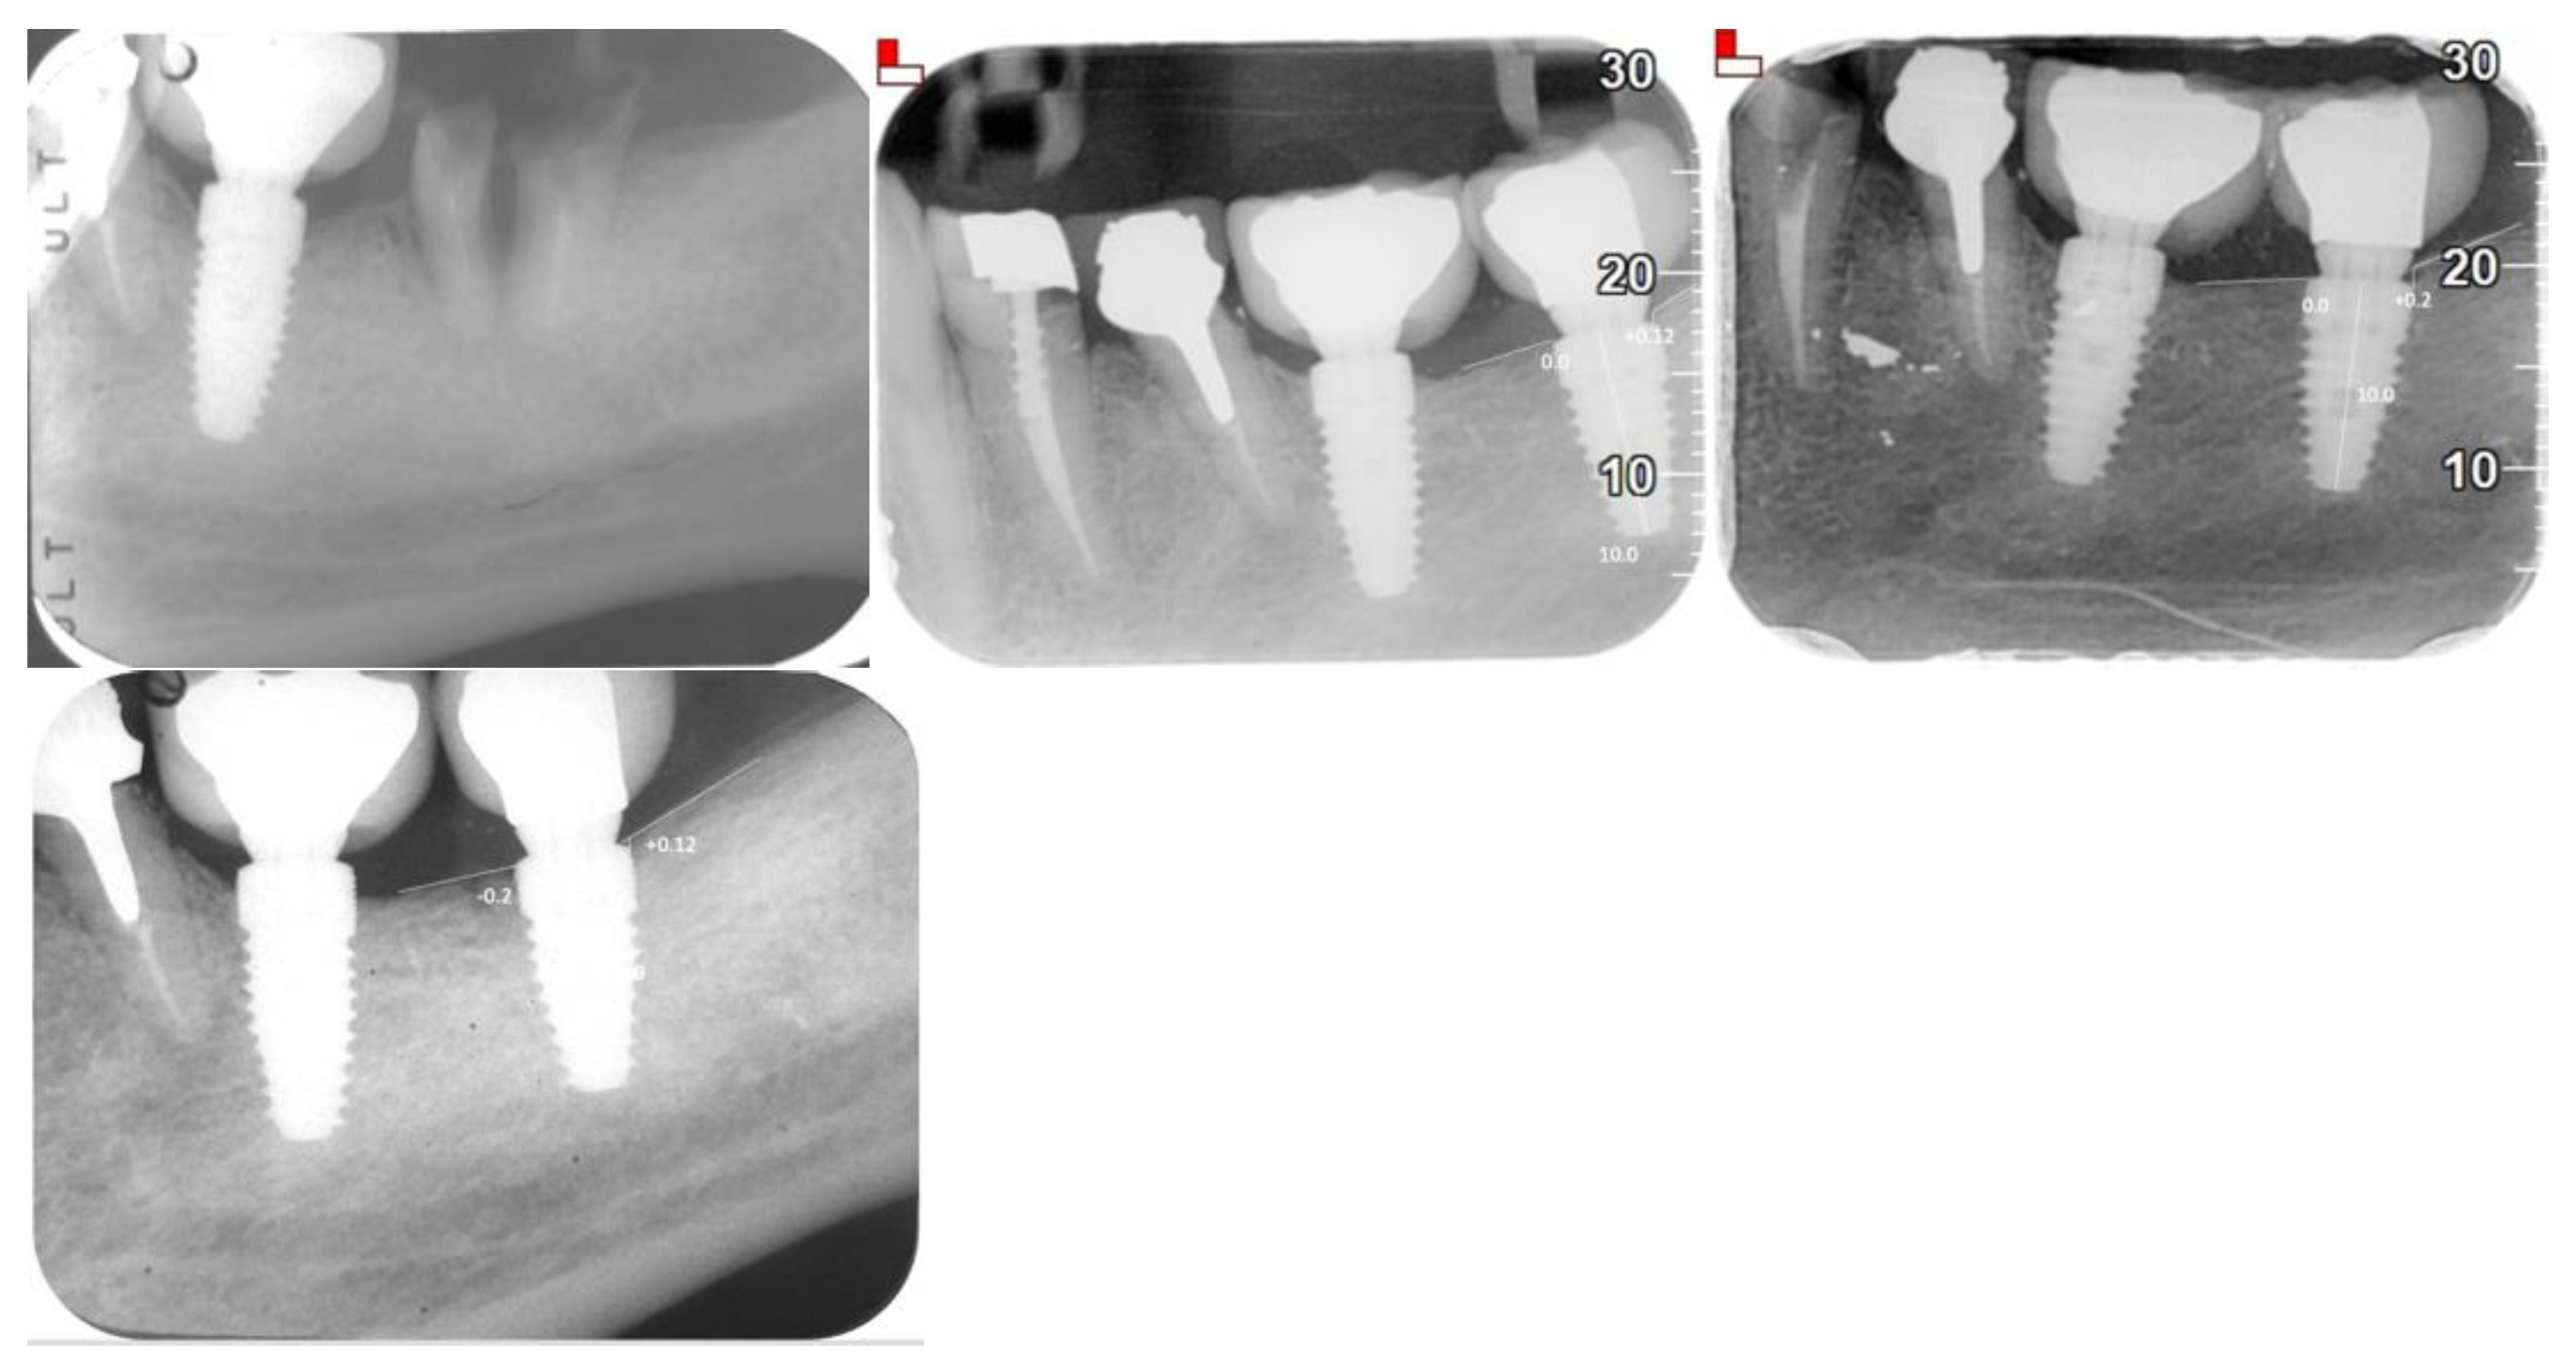

| Evaluation Methods | Orthopantomograms (OPG), cone beam computed tomography (CBCT), intraoral radiographs, clinical examinations |

| Peri-implant Bone Loss | Mean: 0.1208 mm (±0.1307) |

| Mesial Bone Loss | 0.14302 mm (±0.0107) |

| Distal Bone Loss | 0.09934 mm (±0.0143) |

| AVERAGE BONE LOSS | 0.1208 + −0.1307 |

| Mesial bone loss | 0.14302 + −0.0107 |

| Distal bone loss | 0.09934 + −0.0143 |